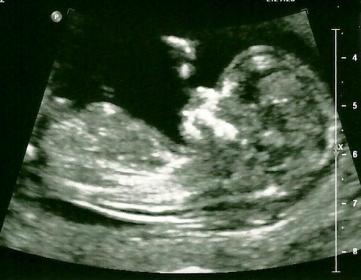

I don't think we have a nub picture here, that I can see anyhow. But I thought it might be fun to see what other members think our SIXTH baby is going off the pictures we do have. :) Thanks in advance! :)

I'd guess girl

Girl x x

i dont think there are any clues x